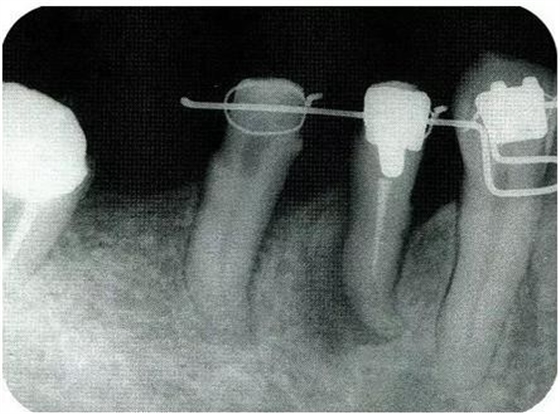

病例5使用正畸進(jìn)行牙齒挺出,讓骨平坦化:

圖18-1(左),2 (右)▲初診時口腔內(nèi)照片和X線片,右下4近中有較深的1壁性骨缺損,右下45有根接近。如果在這個情況下進(jìn)行骨外科處理,需要犧牲較多的右下3遠(yuǎn)中的牙槽骨。也會造成周圍骨形成較大的臺階。

圖18-3▲佩戴臨時冠后,右下4應(yīng)用正畸邊挺出邊向近中移動。結(jié)果改善根接近的問題,右下4近中所存在的較深的骨缺損向右下5和右下4較淺的骨缺損擴(kuò)散。在這個情況下,應(yīng)用牙周外科的處理就會比較合適。